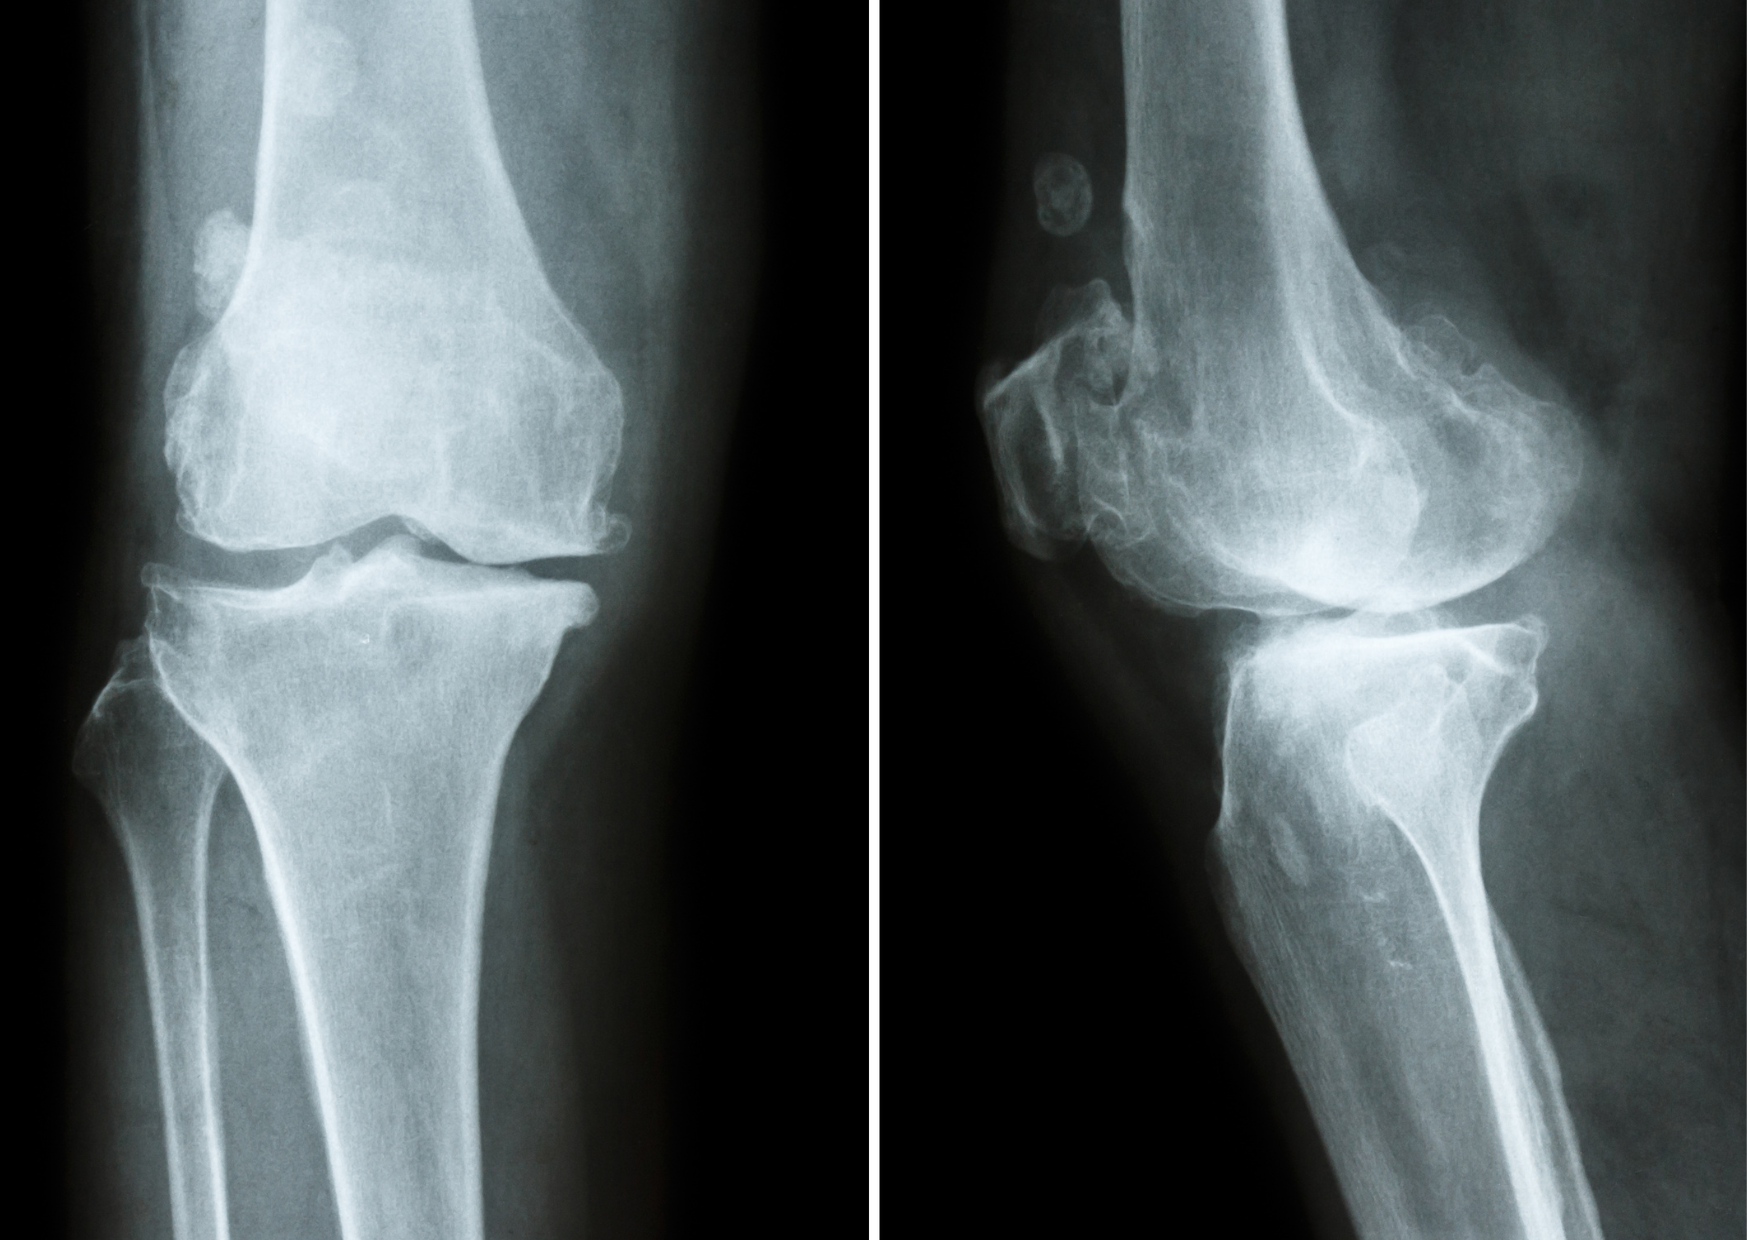

L'arthrose est une affection chronique de l'articulation caractérisée par une altération progressive du cartilage articulaire. Le cartilage est un tissu lisse et élastique qui recouvre les extrémités des os. Il permet le glissement fluide des surfaces articulaires et absorbe une partie des contraintes mécaniques lors des mouvements. Avec le temps ou sous l'effet de contraintes répétées, ce cartilage peut s'amincir, se fissurer ou perdre en qualité. L'articulation devient alors moins souple et moins amortissante et plus sensible aux charges. Mais l'arthrose ne concerne pas uniquement le cartilage. Elle touche également : l'os sous-chondral situé juste sous le cartilage, la membrane synoviale qui produit le liquide articulaire, la capsule articulaire, les ligaments, les fascias et les muscles environnants. L'arthrose est donc une atteinte globale de l'articulation et de son environnement.

L'os sous-chondral, situé juste sous le cartilage, est richement vascularisé et innervé. Lorsque le cartilage s'amincit, les contraintes mécaniques se répercutent davantage sur cet os. Des micro-remaniements, une sclérose osseuse ou une hypersensibilisation des nocicepteurs peuvent alors apparaître, générant une douleur profonde, souvent majorée à l'appui ou lors des mouvements.

Osteoarthritis is a chronic joint condition characterized by progressive deterioration of the articular cartilage. Cartilage is a smooth and elastic tissue that covers the ends of bones. It allows smooth gliding of joint surfaces and absorbs part of the mechanical stress during movement. Over time or under repeated stress, cartilage may thin, crack, or lose quality. The joint then becomes less flexible, less shock-absorbing, and more sensitive to load.

However, osteoarthritis does not involve only the cartilage. It also affects the subchondral bone located just beneath the cartilage, the synovial membrane that produces joint fluid, the joint capsule, ligaments, fascia, and surrounding muscles. Osteoarthritis is therefore a global condition of the joint and its environment.

The subchondral bone, located just beneath the cartilage, is richly vascularized and innervated. When cartilage thins, mechanical stresses are transmitted more directly to this bone. Micro-remodeling, bone sclerosis, or hypersensitization of nociceptors may develop, generating deep pain, often increased with weight-bearing or movement.